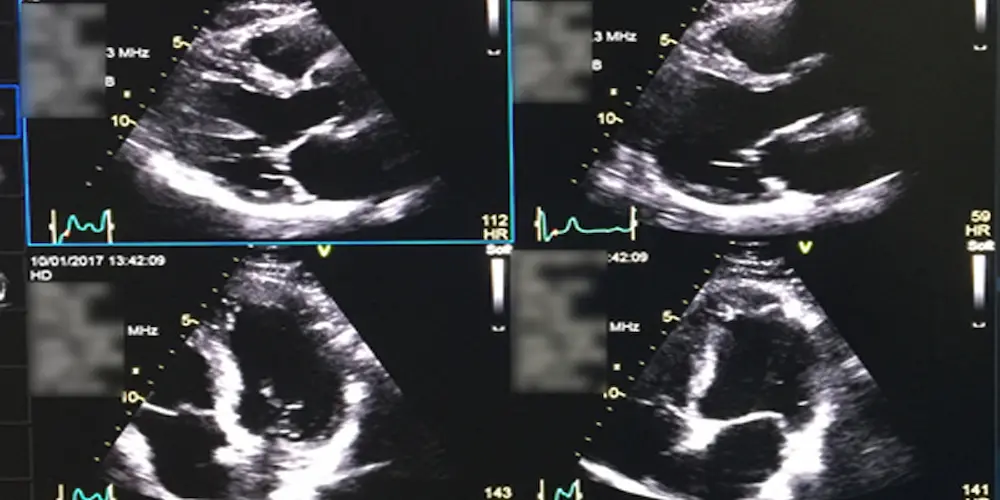

اگر بخواهیم ساده بگوییم، پاسخ به سوال اکو قلب چیست این است: ابزاری دقیق برای تشخیص بیماری‌های قلبی، بررسی عملکرد دریچه‌ها، عضله قلب و اندازه‌گیری جریان خون در قلب، بدون نیاز به جراحی یا تابش اشعه که با استفاده از امواج صوتی (اولتراسوند)، تصاویر زنده‌ای از قلب ایجاد می‌کند. این تصاویر به پزشکان کمک می‌کنند تا ساختار، اندازه، عملکرد و نحوه پمپاژ قلب را بررسی کنند.

پزشک یا تکنسین، دستگاه کوچکی به نام “پروب” را روی سینه حرکت می‌دهد تا تصاویر زنده از قلب روی مانیتور ظاهر شوند.

تصاویر توسط پزشک بررسی و در صورت نیاز ضبط می‌شود تا ساختار، دریچه‌ها و پمپاژ قلب به‌دقت ارزیابی شود.